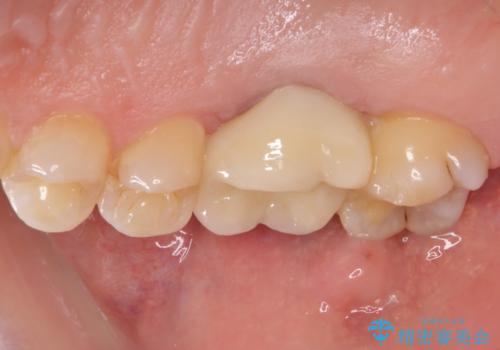

歯周外科処置を併用した奥歯の補綴治療

- クラウンが装着された奥歯から、歯磨きの度に出血するとのことで来院された患者様です。

虫歯が歯肉の奥深くにまで及んでおり、歯肉が腫れやすい状態となっていたため、歯肉の切除並びに歯槽骨の形態修正を行い、虫歯が歯肉の外に出てくるようにした上で、オールセラミックにて補綴することとしました。

歯間ブラシを通す度に出血をするのは、ご自身の磨き方が悪いからと思っていらっしゃいましたが、治療後は全く出血することがなくなり、患者様には大変満足していただきました。